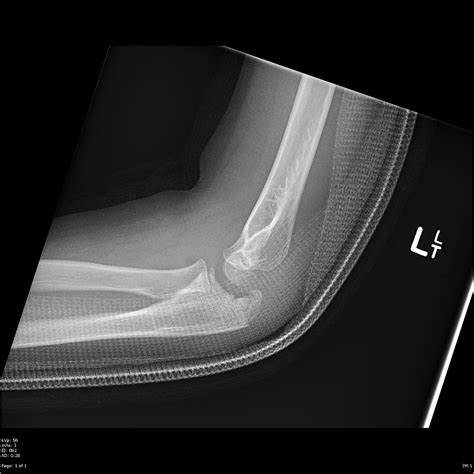

• X-rays: These can help identify fractures, dislocations, and other bony abnormalities.

• CT Scans: Computed tomography scans can offer a more detailed view of the bone structure and help identify complex fractures.